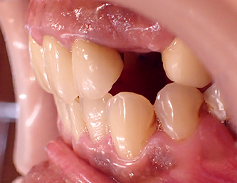

- ブリッジ 症例写真 B-0112FZC3本 女性モニターの方です。

この方は奥歯が虫歯で根だけになってしまっていました。 この歯は抜歯し、ブリッジで治しました。 当院では強度が高く色がきれいなジルコニアブリッジで治しております。 歯型を取らずに、口腔内スキャナーでジルコニアブリッジを作成しますので、精度の高いブリッジを入れることが可能です。 治療回数は3回でした。